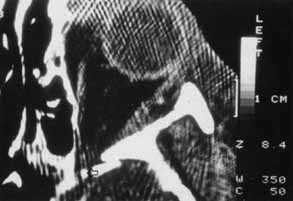

Orbital emphysema results from air forced from the sinus into the orbit. This condition can occur with nose blowing or when orbital fat functions as a ball-valve over the fracture site.53 Emphysema of the soft tissue is appreciated by crepitus that can be palpated in the inflated eyelids. When the orbital septum remains intact, air is confined in the orbital space and can result in proptosis or reduction in motility (Fig. 12). Elevation of intraocular and intraorbital pressure can potentially compromise the retinal or posterior ciliary vasculature. Vision loss from this mechanism has been described,50,54,55 and this loss is considered an ophthalmic emergency. Intervention may include aspiration of air from an accessible site, such as the conjunctiva,50 or lateral canthotomy, with or without cantholysis, to decompress the orbit.52,54 More often, the condition is not sight-threatening and is self-limited. To avoid further inflation, the patient should be advised to not blow the nose or generate a Valsalva maneuver.

Fig. 12 In this patient (A) with right medial wall and tripod fracture, the mass effect of orbital air (B) (arrow) causes exophthalmos and contributes to hypophthalmos.